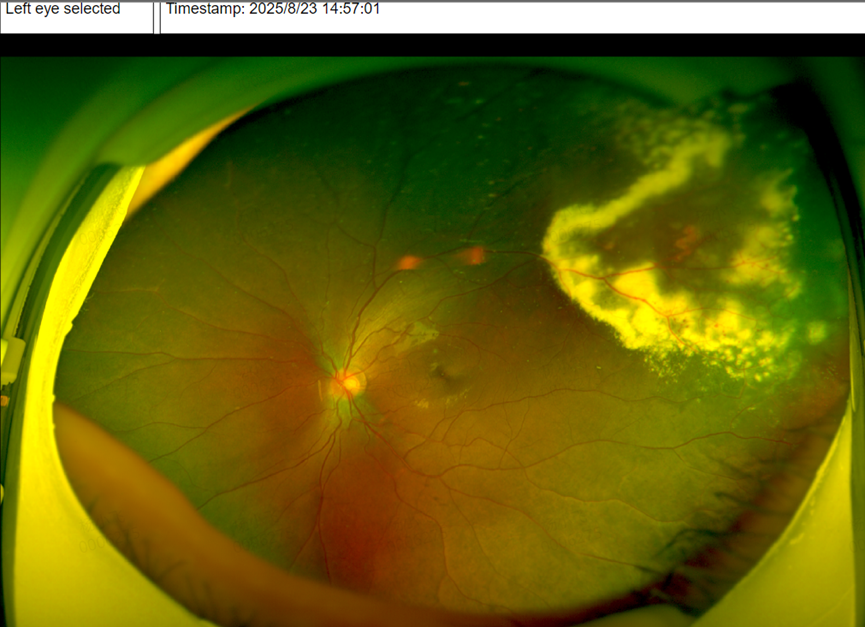

可检查结果让所有人揪心——孩子左眼患上了「外层渗出性视网膜病变(Coats 病)」,这是一种多见于儿童的眼底疾病,早期症状隐匿,很容易被忽视。幸运的是,由于筛查及时,孩子已被迅速转诊至辽宁爱尔眼科医院眼底专家团队,后续将接受针对性治疗,为保住视力争取到了宝贵时间。

「如果当时只查了近视度数,没做眼底检查,这个孩子的病情可能会被继续耽误,等到出现明显症状时,视功能损伤可能已经不可逆了。」爱尔眼科辽宁省区副总院长杨积文教授对此深有感触,也希望通过这个案例,让更多家长重视儿童眼底筛查的重要性。

而确诊 Coats 病,需要依靠专业的眼科检查,比如「荧光素眼底血管造影」(能清晰看到眼底血管的异常扩张)、「眼部 B 超」,必要时还会做 CT 检查,用来和其他类似疾病(如视网膜母细胞瘤)区分开,避免误诊。